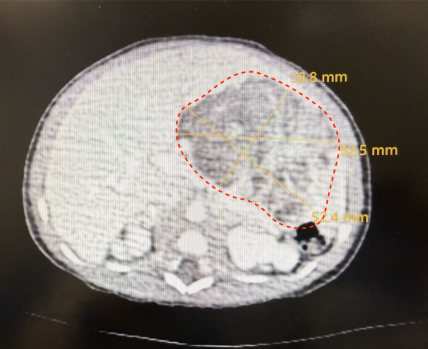

一场需要护航的增强CT 手术的成功,始于术前一次至关重要的“精准侦察”——针对新生儿的多学科协作增强CT检查,这远非一次普通的拍片。“新生儿的增强CT检查,本身就是一次高难度的多学科配合演练。”医学影像科郭建新主任介绍。由于患儿肿瘤血供复杂,位置紧邻重要血管与脏器,必须通过静脉注射造影剂进行增强扫描,才能获得清晰的“作战地图”。然而,新生儿血管细如发丝、循环系统脆弱,造影剂的剂量、流速必须极度精确,且检查过程中患儿必须绝对安静,任何移动都会导致图像失效。这就需要一个精密配合的“铁三角”:儿童外科医生提出对影像的具体需求;医学影像科团队量身定制低辐射剂量、快速扫描方案,并精确计算造影剂用量;在麻醉科团队协作下,最终生成了清晰的显示肿瘤与周围组织结构关系的CT图像,为手术精准并完整切除肿瘤病灶提供了可靠依据。

多学科汇流,决胜手术与术后监护 有了影像与麻醉基础,手术室里筑起的生命支撑平台上,陆港儿童外科刘仕琪教授团队开始了肿瘤精准切除。在术前影像检查定位与指引下,术中顺利分辨出巨大肿瘤从患儿胃壁长出。在手术团队精确操作下,历时2小时40分钟,肿瘤被完整切除,术中有效保护好相邻重要器官与组织。术后患儿按计划转入新生儿科监护室监护,目前患儿已顺利脱离呼吸机,开始喂养,即将从新生儿重症监护室转入普通病房。

病理报告明确“胃来源的未成熟畸胎瘤III级”(胃恶性畸胎瘤)。综合不同时期的文献报道,全球范围内报道的病例总数不足100例,新生儿更为罕见。